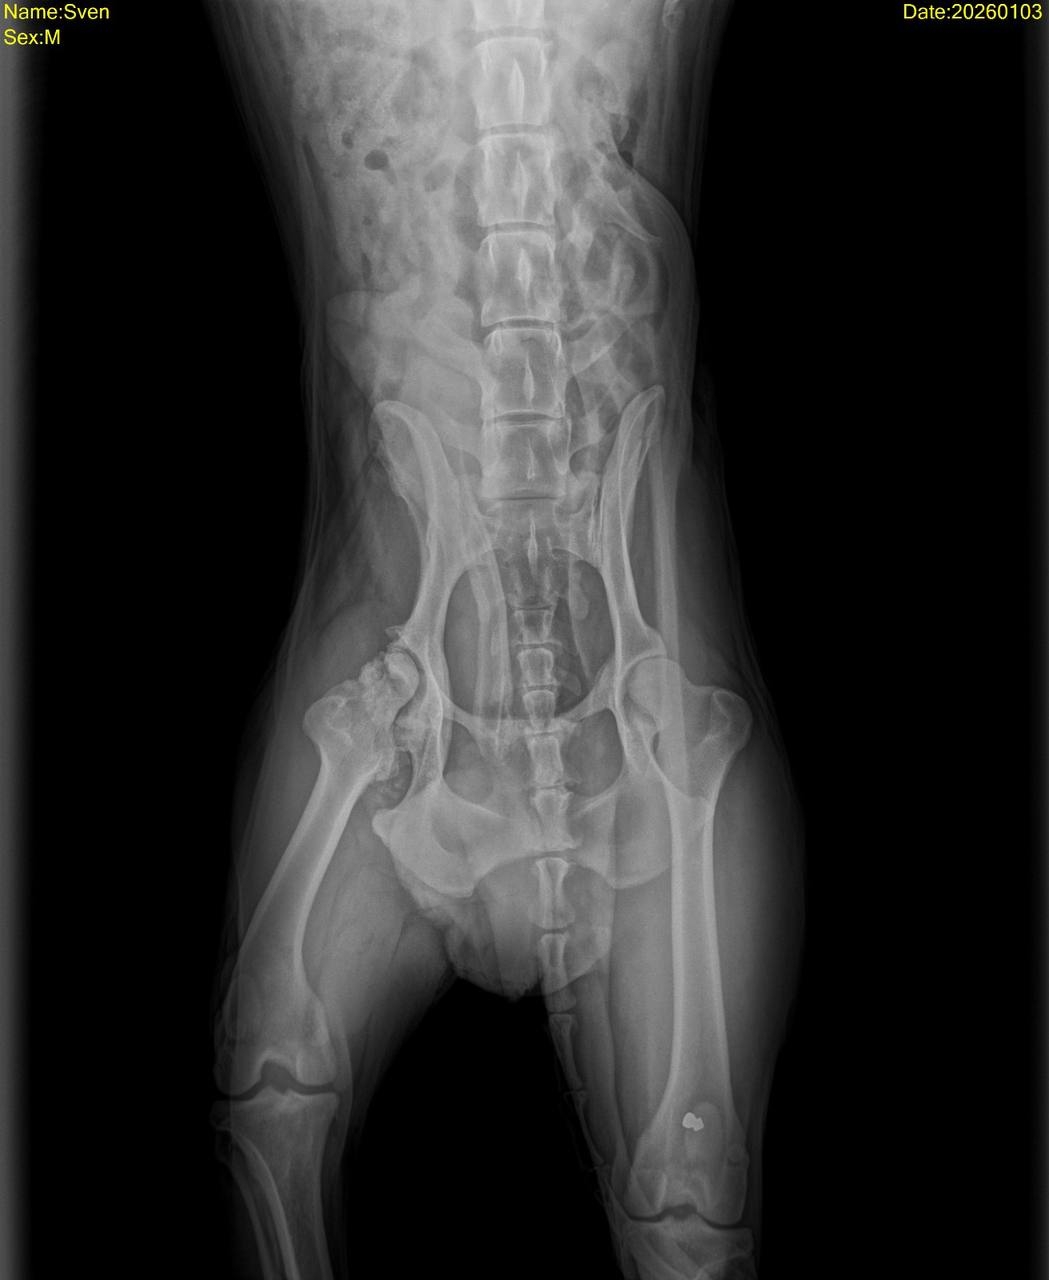

В Свена стреляли и сбили машиной, у него перелом, который требует срочной операции, так же собаке необходимо МРТ.